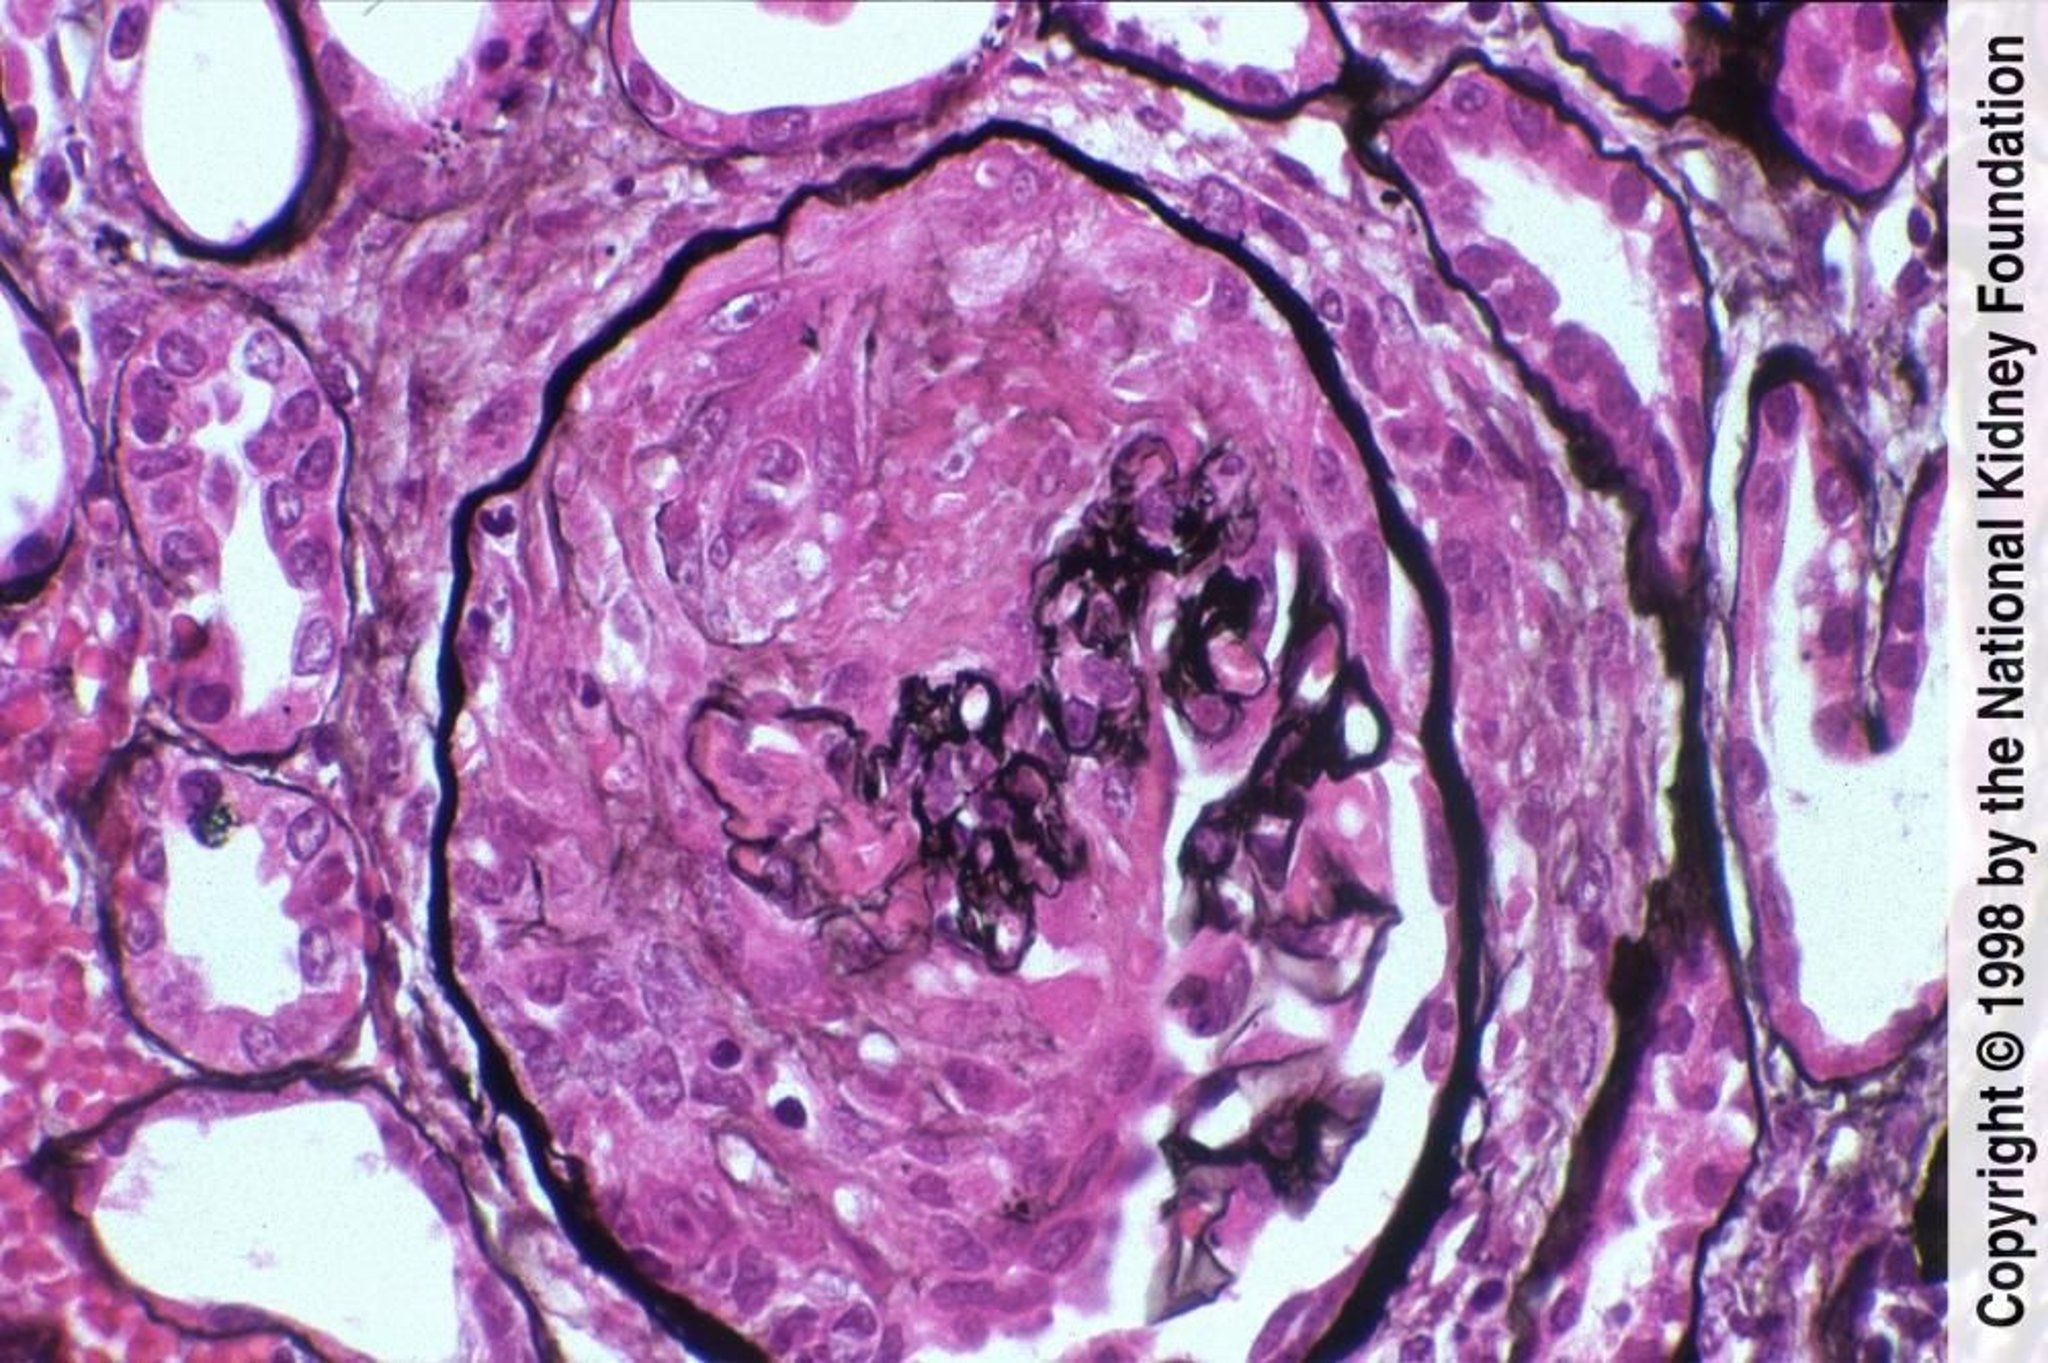

Rasch progrediente Glomerulo- nephritis (pauci-immun)

Die Pauci-Immunerkrankung ist durch Halbmondbildung mit fibrinoider Nekrose und negativer Immunfluoreszenzfärbung gekennzeichnet (Jones-Silberfärbung, ×400).

Image provided by Agnes Fogo, MD, and the American Journal of Kidney Diseases' Atlas of Renal Pathology (see www.ajkd.org).